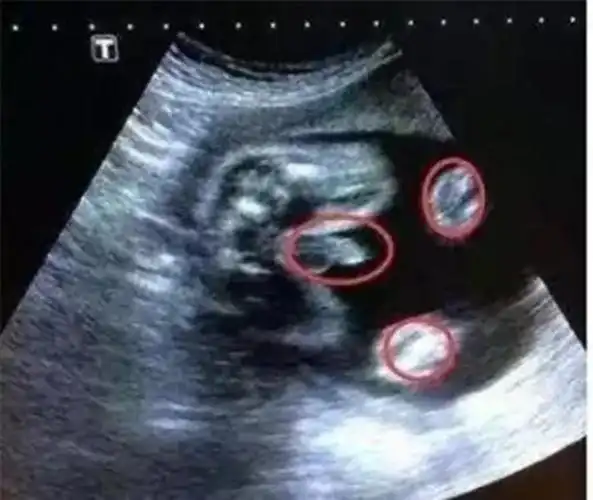

千家万户!三个月男女胎儿区别图"春意盎然"-第1张图片-断秋风网